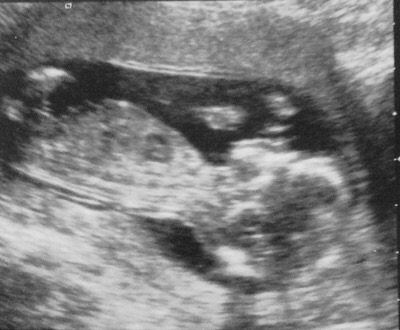

Still got over 3 weeks till our next scan and the suspense is killing me so any guesses would be very welcome :)

I don't really think there is a nub here, its possible one is there but it is a blurry pic, if what I see is a nub girl lean, but picture is just not that great!